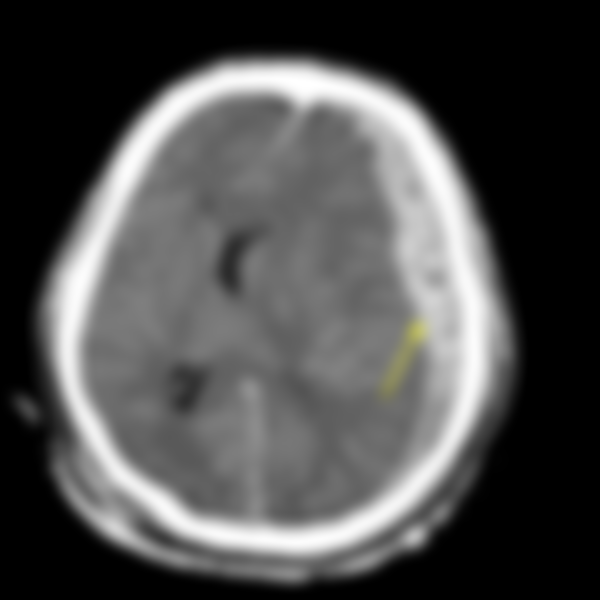

78.1.箭號所指,出血處為何?

(A)硬膜下腔

(B)硬膜外腔

(C)蛛網膜下腔

(D)腦室

A(51), B(37), C(1499), D(465), E(0) #1150477

血液會順著蛛網膜下腔流竄